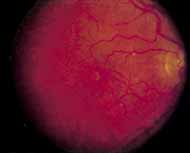

During the early stage of the dystrophy, when patients demonstrate a slight-to-moderate decrease in visual acuity and minimal color defects, there are minor or no visible fundus abnormalities. At most, the foveal reflex may be absent and there may be some increased granularity of the retinal pigment epithelium in the macula. Later, there is a decrease of visual acuity to the 20/400 range, oval atrophy of the macular retinal pigment epithelium (“beaten bronze” atrophy), and associated choroidal atrophy (Fig. 3). A characteristic bull's-eye maculopathy, similar to that seen in patients with chloroquine retinopathy, may also be seen.90 Photophobia, occasional nyctalopia, incomplete-to-complete color defects, and a central scotoma are often present. The symmetry of the process in both eyes is remarkable.